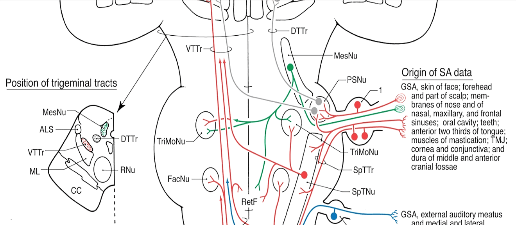

This prolonged friction termed the posterior Disclusion Time3,12 when longer than 0.5 seconds duration triggers excessively long tooth pulp and Periodontal Ligament (PDL) nerve transmissions that afferently communicate directly (without an intervening synapse) with both the Trigeminal Motor Nucleus (TrMoNU) and the brain’s Reticular Formation (RetF), a major brain center that controls swallowing, sleep, posture, sexual function, circulation, and breathing (Figures 2, 3, 4).1,2 These nerve transmissions occur thousands of times per day as patients chew, eat and swallow. Once in the RetF, these posterior teeth nerves directly influence outgoing nerve transmissions to the muscles and structures associated with continuously breathing while chewing food and swallowing, ensuring food enters the digestive tract rather than the lungs. Without this specialized tooth-induced neural control, food in the airway and lungs would choke and asphyxiate humans.

Figure 2 – The green nerve pathway emanates from molar and premolar pulp and PDL mechanoreceptors passes through the Mesencephalic Nucleus (MesNU) to synapse in the Trigeminal Motor Nucleus (TrMoNU) and with the Reticular Formation (RetF). Reprinted from Haines Neuroanatomy, 8Th Ed., Lippincott, William, and Wilkins publishers, http://lww.com)